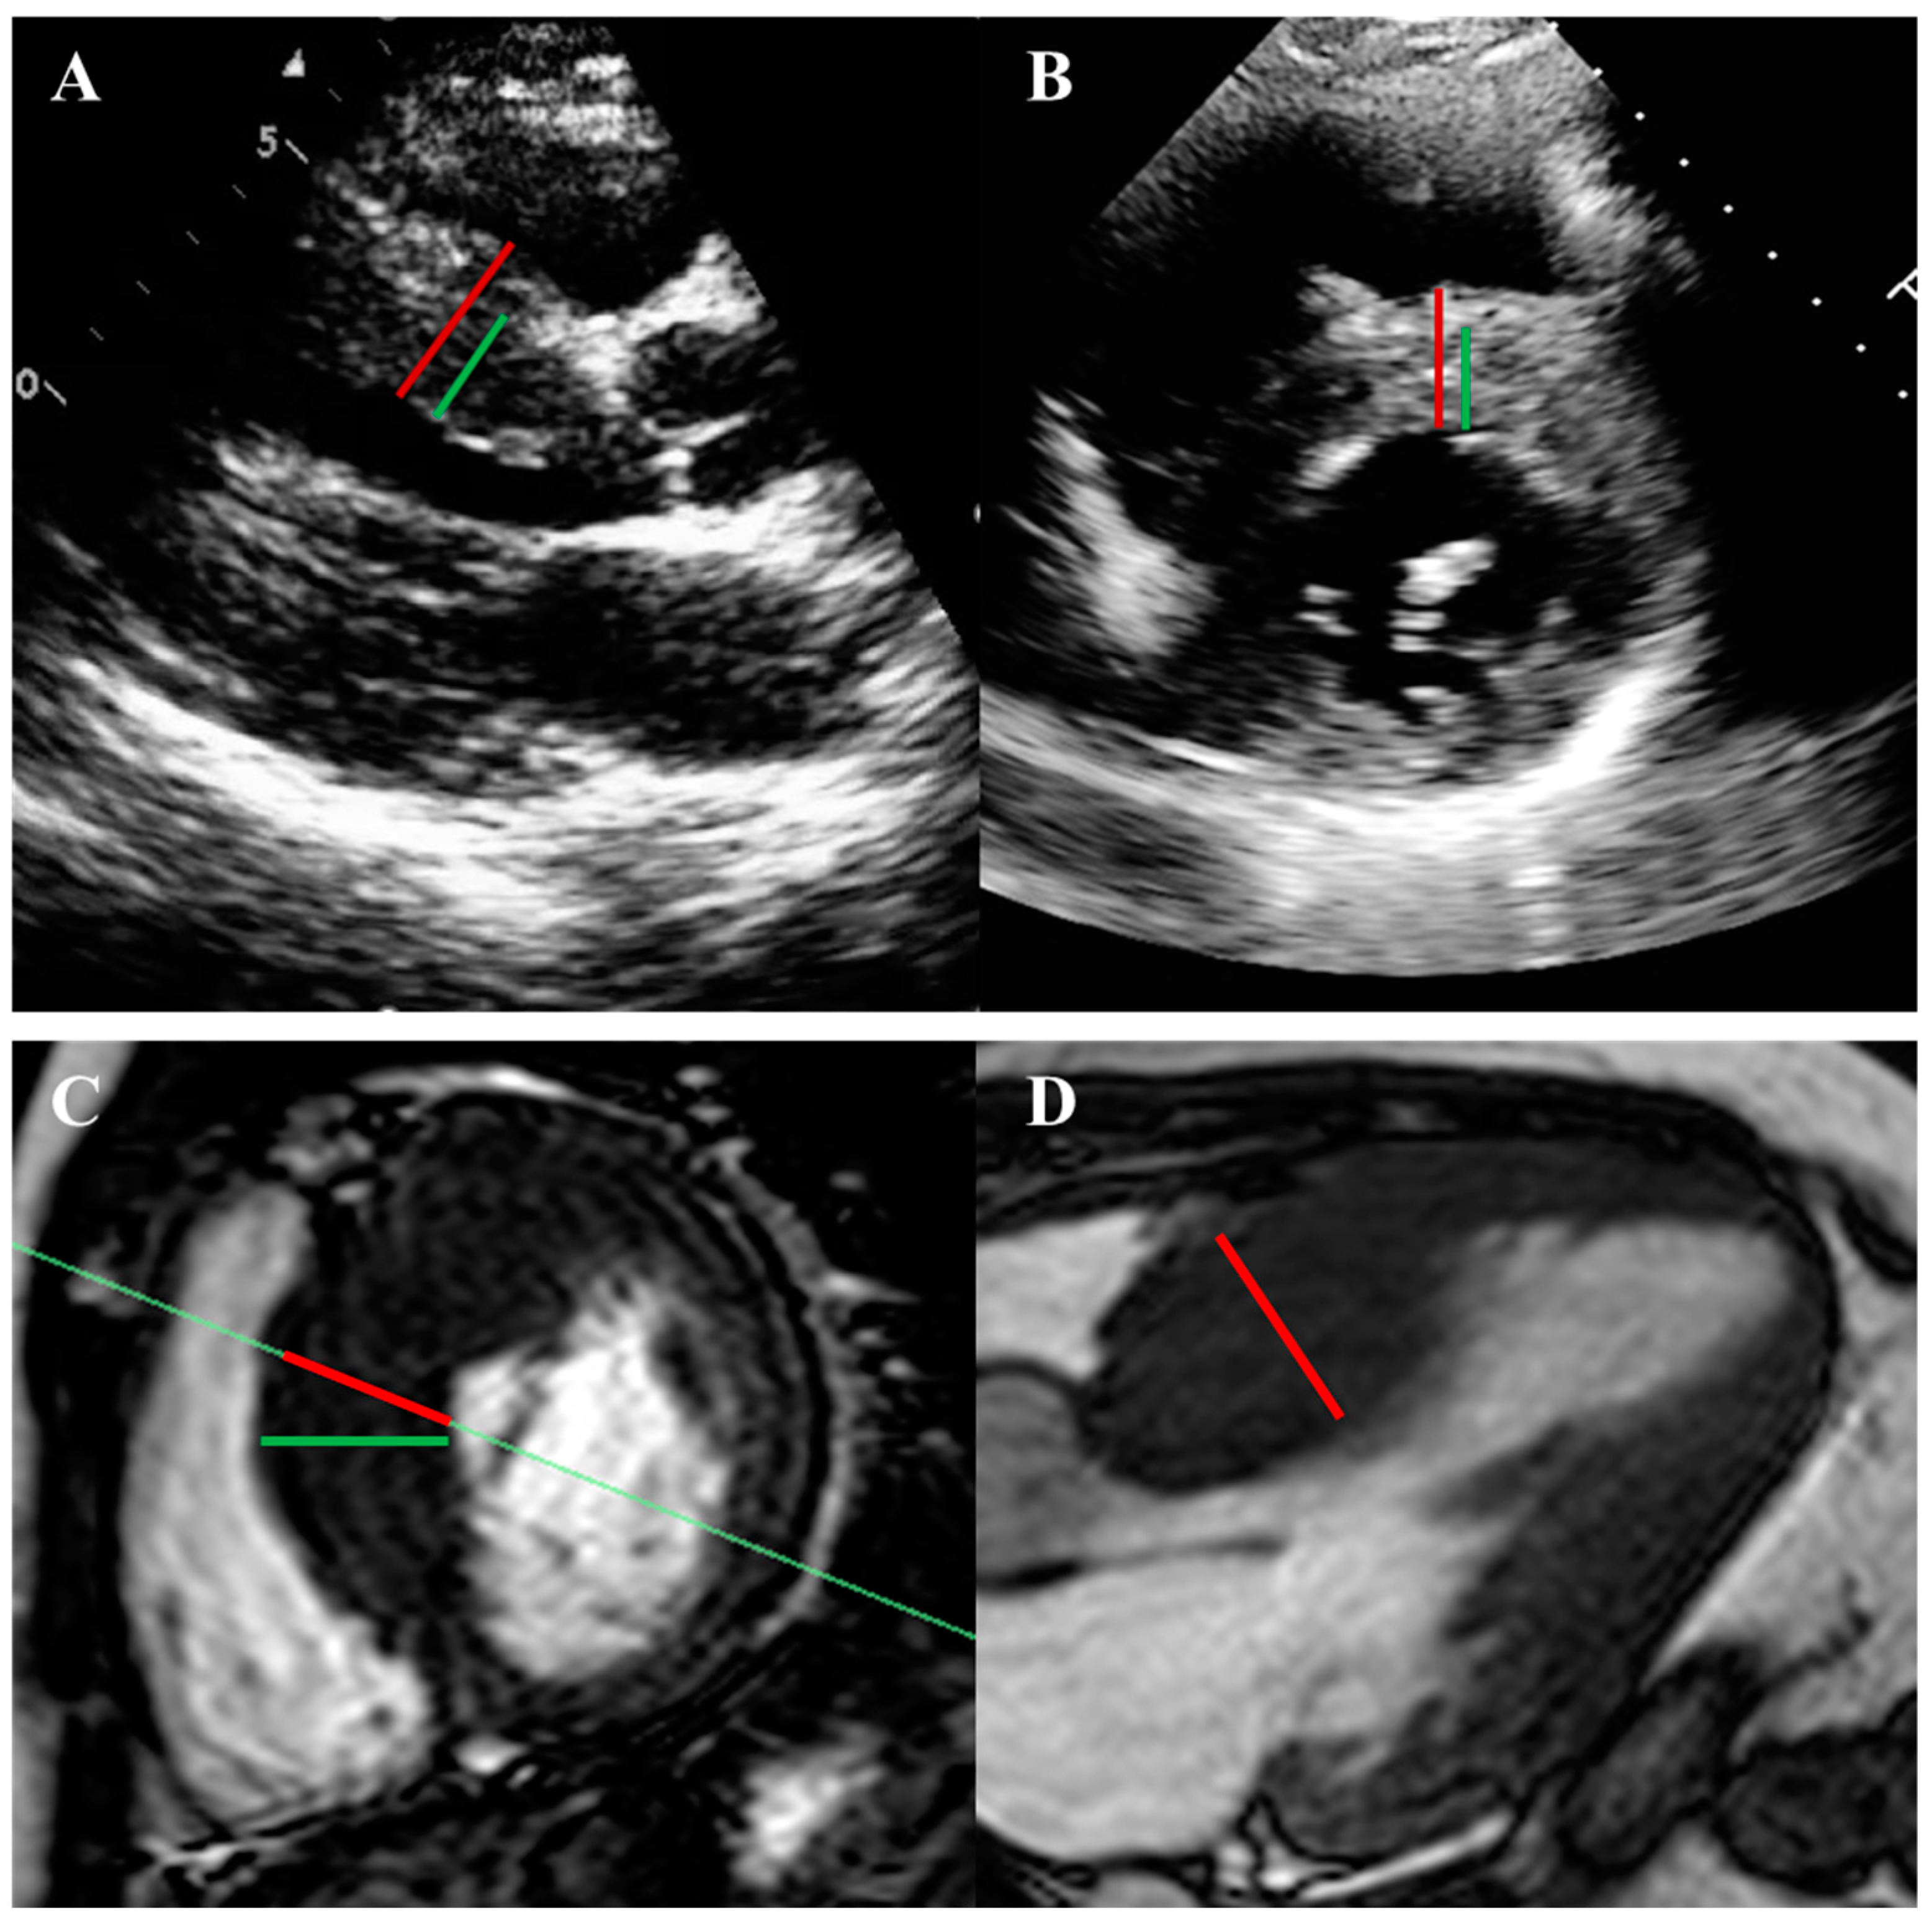

2.1. Left Ventricular Hypertrophy and Morphology

- Moon, J.C.; Fisher, N.G.; McKenna, W.J.; Pennell, D.J. Detection of apical hypertrophic cardiomyopathy by cardiovascular magnetic resonance in patients with non-diagnostic echocardiography. Heart 2004, 90, 645–649. [Google Scholar] [CrossRef]

- Maron, M.S.; Rowin, E.J.; Maron, B.J. How to Image Hypertrophic Cardiomyopathy. Circ. Cardiovasc. Imaging 2017, 10, e005372. [Google Scholar] [CrossRef]

- Rickers, C.; Wilke, N.M.; Jerosch-Herold, M.; Casey, S.A.; Panse, P.; Panse, N.; Weil, J.; Zenovich, A.G.; Maron, B.J. Utility of cardiac magnetic resonance imaging in the diagnosis of hypertrophic cardiomyopathy. Circulation 2005, 112, 855–861. [Google Scholar] [CrossRef]

- Hindieh, W.; Weissler-Snir, A.; Hammer, H.; Adler, A.; Rakowski, H.; Chan, R.H. Discrepant Measurements of Maximal Left Ventricular Wall Thickness Between Cardiac Magnetic Resonance Imaging and Echocardiography in Patients with Hypertrophic Cardiomyopathy. Circ. Cardiovasc. Imaging 2017, 10, e006309. [Google Scholar] [CrossRef] [PubMed]